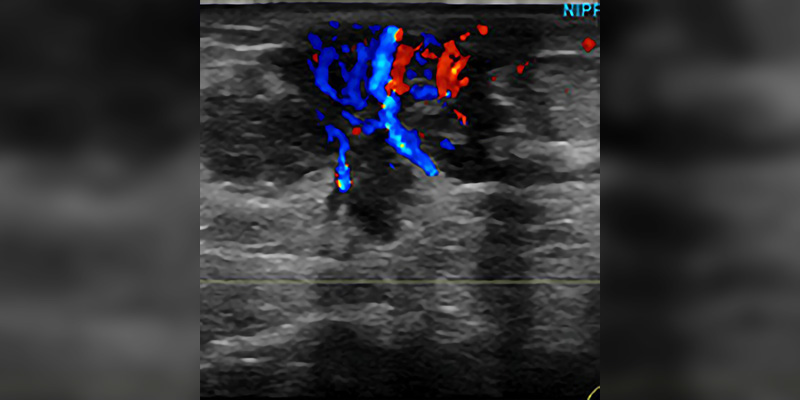

Breast Sonography Registry Review

The following study materials and resources are suggested by experienced R.T.s to help you prepare for the breast ultrasound certification exams offered by the American Registry of Radiologic Technologists and the American Registry for Diagnostic Medical Sonography.